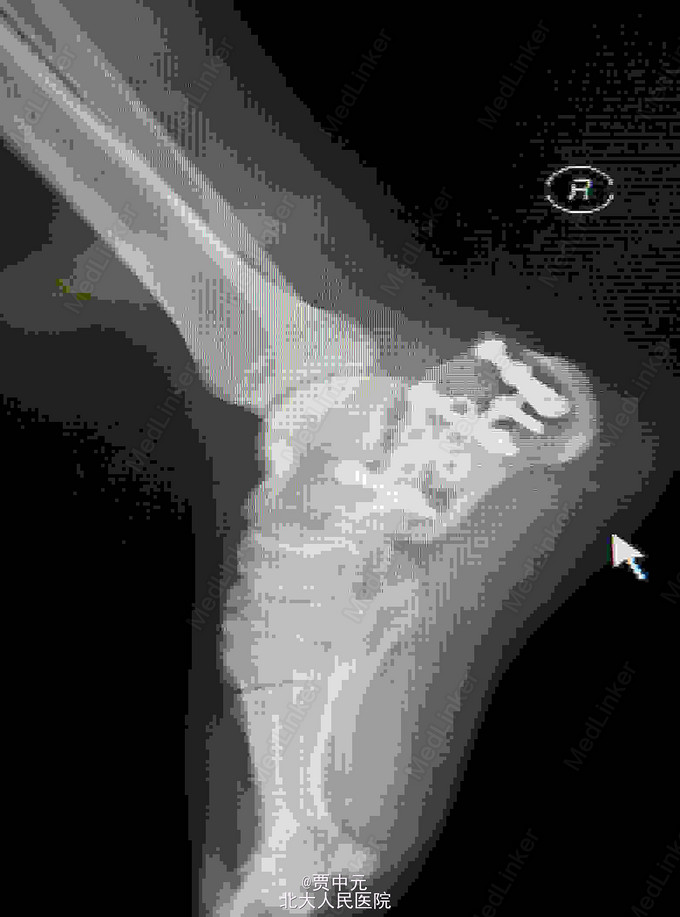

男性,31岁,主因“高处坠落伤致右足跟部疼痛,活动受限1天”于急诊以“右侧跟骨骨折”收入院。 一.病例特点 1.青年男性,高处坠落史。 2.患者约1天前自高处坠落右足着地,当时未昏迷,自觉右足肿痛,不敢活动,在当地医院拍片示:右侧跟骨骨折,为进一步手术治疗收住院。自入院来,患者无发热及胸闷憋气及腹痛症状

入院查体:右足跟部肿胀,局部皮下淤血,压痛,叩击痛,趾端血运可,足趾感觉及活动可,余肢体未见明显异常。 X线:右侧跟骨骨折(外院)

右侧跟骨骨折:高处坠落伤1天,查体:右足跟部肿胀,局部皮下淤血,压痛,叩击痛,趾端血运可,余肢体未见明显异常。 X线:右侧跟骨骨折(外院),根据外伤史,查体及X线检查,故此诊断明确

入院后考虑患者伤足局部软组织损伤重,皮肤条件欠佳,予以消肿,待皮纹征阳性后于今日在椎管内麻醉下行右跟骨骨折切开复位植骨内固定术。